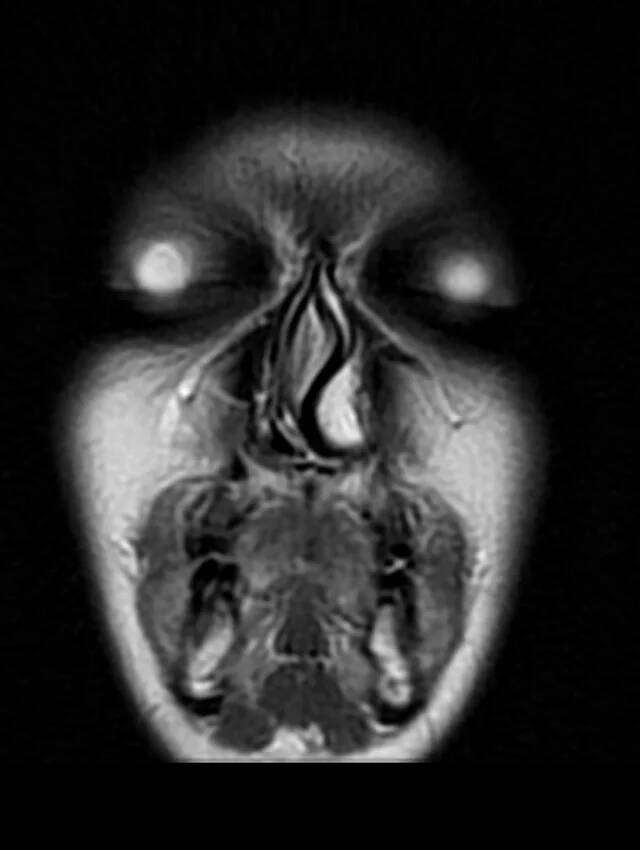

If you've ever had an MRI, you probably know just how wild the imagery can be. It's like an x-ray on steroids. If you've ever had an MRI done of your face, you're probably still recovering from the trauma.

After all, this is what a facial MRI looks like: Gleaming, soulless eyes with no pupils, an unsettling swirl of a nose, and a gaping mouth. On the one hand, it's cool to see. On the other, it's hard not find this off-putting.